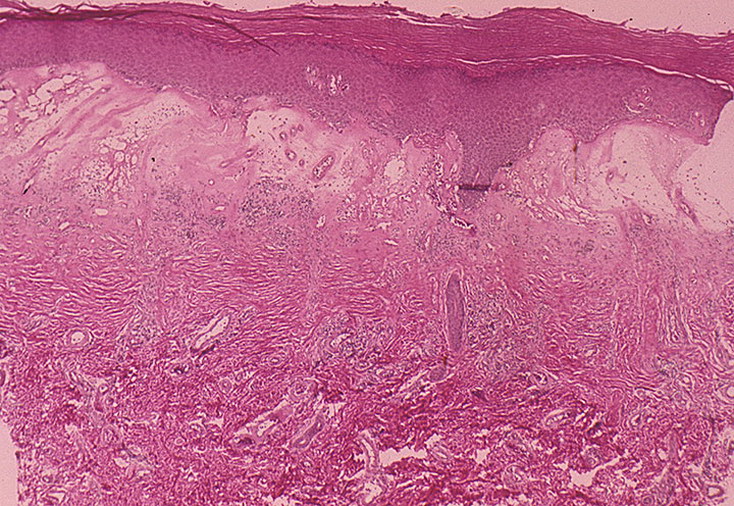

Фото Красного Плоского

Фото Красного Плоского 103 фото